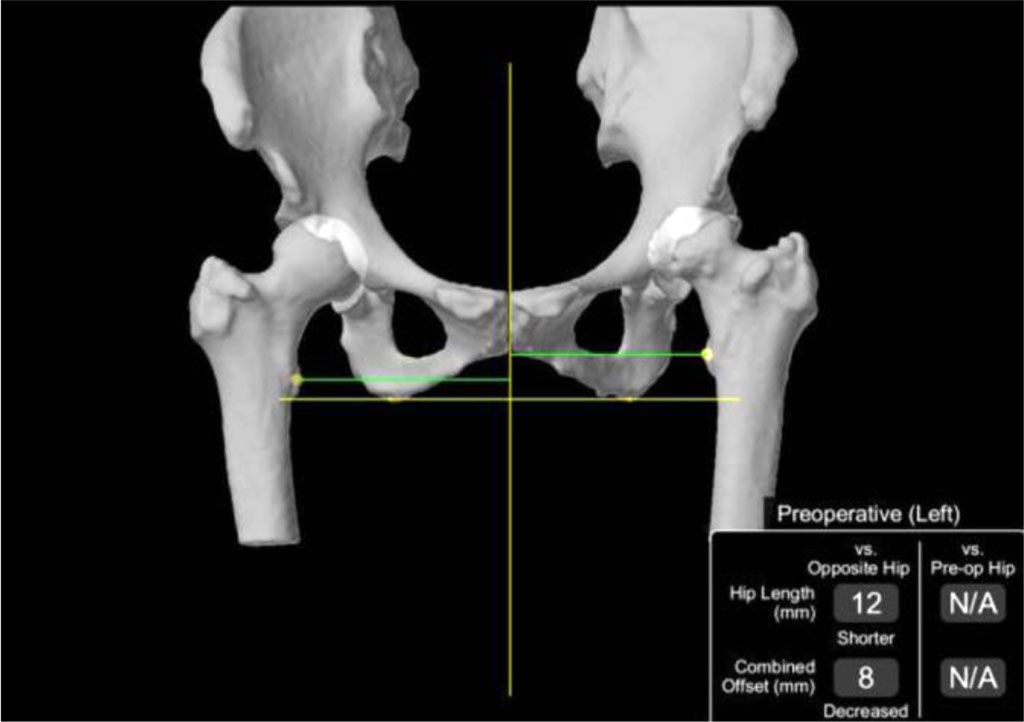

Another useful tool is preoperative three- dimensional modeling, which enables the development of a surgical strategy, reduces operation time, and helps prevent complications arising from individual anatomical variations. This approach significantly facilitates a personalized treatment plan for each patient [47]. Research results show that the use of robotics employing computed tomography (CT) and 3D reconstruction improves radiological outcomes by increasing the safe placement of the prosthesis compared to the manual technique. Studies do not indicate any significant difference in intraoperative or early postoperative complications compared to the manual technique. Despite promising short-term results, there is a lack of comprehensive studies with longer follow-up periods that could confirm the long-term impact of using surgical techniques supported by robotic tools [48].

Fig 6. Three-dimensional reconstruction of anatomical structures [49].

Fig 7. Screen displaying preoperative confirmation of the femoral stem size, offset, and version prior to cutting the femoral neck. [49].